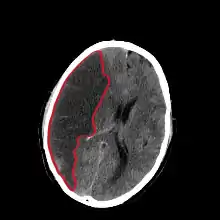

CT scan slice of the brain showing a right-hemispheric cerebral infarct (left side of image).

Computed tomography (CT) and MRI scanning will show damaged area in the brain. A CT scan will rule out a hemorrhagic stroke, is cheaper for the patient, and can be found in almost all hospitals unlike an MRI machine.[25][26] Once the Doctor rules out a hemorrhagic stroke, rTPA can be given.[25] An MRI can help to diagnose an acute cerebral infarct as quickly as 6 hours from start of symptoms,[25] It can also help time when the stroke happened.[27] The biggest problem with an MRI is it can't be done on a patient with certain metallic implants or if the patient is claustrophobic.[28] A head and neck CT angiogram can be performed within 6 hours of onset of symptoms to see where the occlusion may be located which can help in determining the cause of the stroke.[29] In people who die from a stroke an autopsy can reveal additional diseases or conditions beyond the stroke itself, as well as uncover uncommon causes of a stroke.[30]